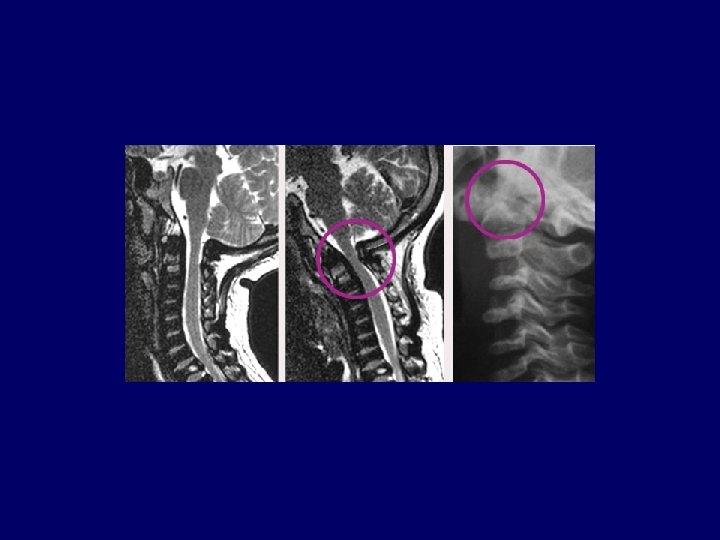

Clinical Problems in MPS IV • Cervical instability • Airway obstruction • Restrictive airway disease

CT Cervical Spine Normal Morquio